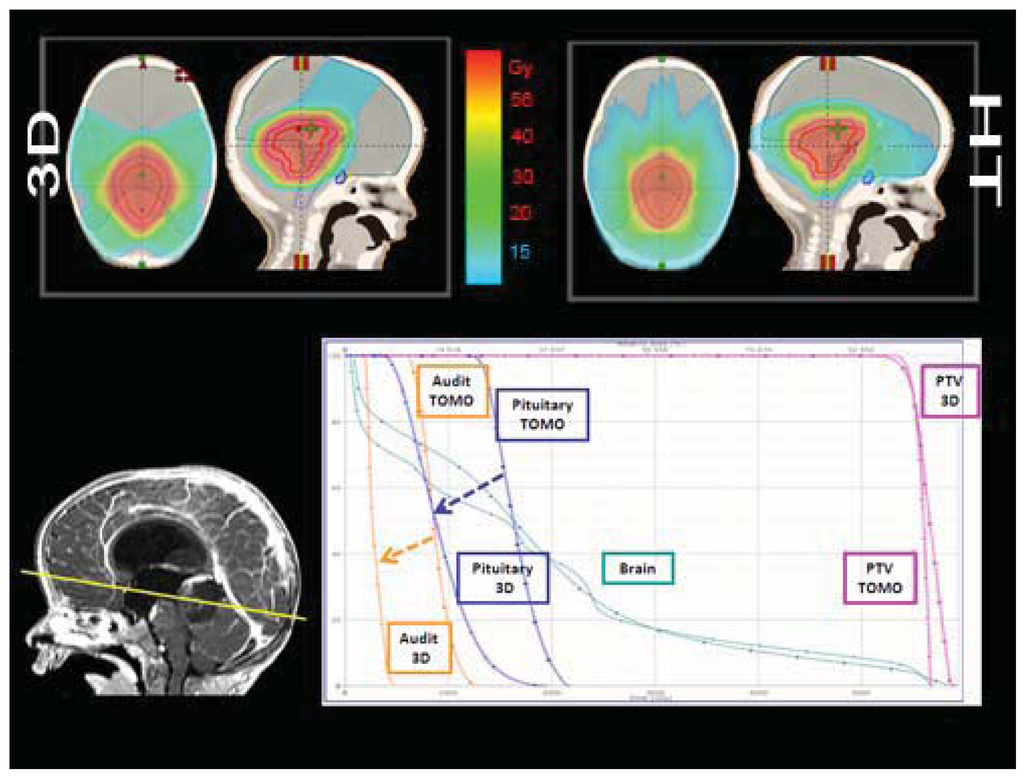

Structures contoured as OARs for the brain patient group were both parotids, teeth, the mandible (including temporo-mandibular joint), the spinal cord, optical structures (optical nerves, chiasm, eyes, lens), the brain, the brain stem, the pituitary gland, temporal lobes, the cochlea, and the thyroid gland. The choice of sparing one organ‘more than another’ is a complex clinical and technical challenge. The use of delivery systems with a very high degree of freedom, such as HT, could permit us to explore the potential of sparing other structures and tissues that normally cannot be efficiently spared with more conventional 3D-CRT or IMRT techniques [9]. Examples of OARs are the cochlea and the pituitary gland in the treatment of the brain. Much importance is given to the prevention of hearing loss as it could compromise the quality of life of these young and very young patients, especially in the workplace and during social relations. Despite its small size (mean volume 0.14 cc), the cochlea is easily identified on CT planning with 3 mm cut [10]. We slightly expanded the anatomic cochlea contour as an OAR to facilitate its preservation from excessive radiation because of its small size. In fact, the value of data resulting from HT planning optimization is not so accurate for OARs whose volumes are lower than 2 cc. Neuroendocrine disturbances in anterior pituitary hormone secretion are common following radiation damage, the severity and frequency of which correlate with the total radiation dose delivered to the hypothalamus-pituitary axis and the time that has elapsed since treatment. Classically, growth hormone (GH) is the most sensitive of the anterior pituitary hormones to irradiation, followed by gonadotrophins, adrenocorticotrophic hormone (ACTH) and thyroid-stimulating hormone (TSH). The somatotrophic axis is the most vulnerable to radiation damage and GH deficiency remains the most frequently seen endocrinopathy. In our example of a 2-year-old male with an atypical teratoid rhabdoid tumor of the quadrigeminal region, the HT plan has been compared with 3D-CRT using no-coplanar fields. The tightly conformal dosimetric characteristics of HT were not advantageous with respect to the cochlea and pituitary gland DVHs. In this case, the relatively small volume of treatment, the regular target volume and the opportunity to choose the entrance fields with CRT, favored applying the latter option (Figure 2). Some patients with brain tumors need CSI and, in this case, HT has a frequent application. In our experience in a 4 year-old-male affected by medulloblastoma treated with HT (Figure 3), an inspection of DVH reveals excellent conformal quality both for CTV brain and spinal cord with better sparing of OARs close to the target [7]. In comparison with conventional techniques, CSI delivered with HT is able to achieve better dose homogeneity and conformality in the target volume. With HT-CSI lower doses are distributed to larger volumes and higher doses to smaller volumes, with higher doses confined to a very small volume. The potential drawback of the low dose bath is that it could have an effect on acute toxicities (e.g., on the lung, on the gastrointestinal tract) and on the total body ID [7].